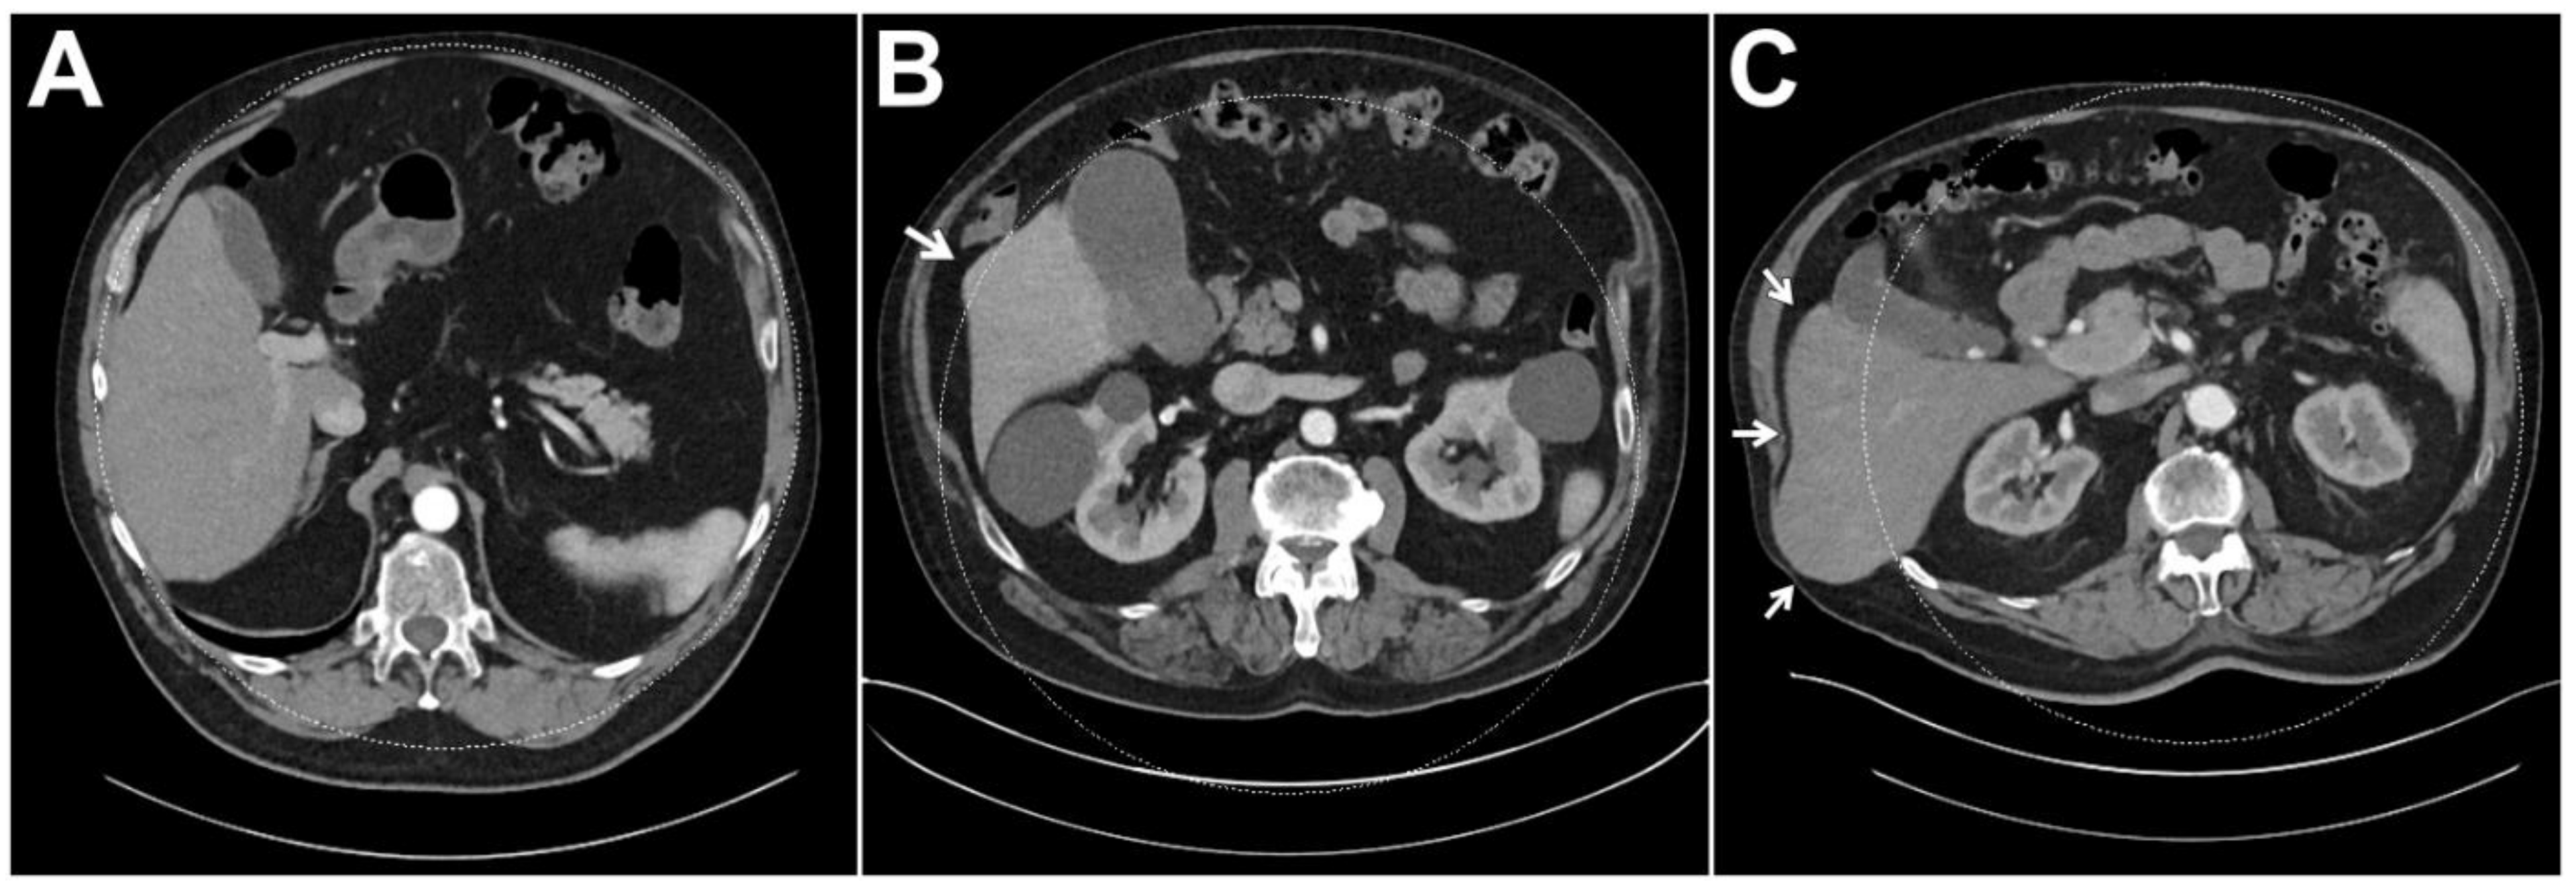

| Full coverage of liver parenchyma in the DE-FOV | 238 (94.1%) | 110 (100%) | 70 (95.9%) | 58 (82.9%) |

| <1 cm of liver parenchyma outside of the DE-FOV | 5 (2.0%) | 0 (0%) | 0 (0%) | 5 (7.1%) |

| 1–2 cm of liver parenchyma outside of the DE-FOV | 5 (2.0%) | 0 (0%) | 3 (4.1%) | 2 (2.9%) |

| >2 cm of liver parenchyma outside of the DE-FOV | 5 (2.0%) | 0 (0%) | 0 (0%) | 5 (7.1%) |